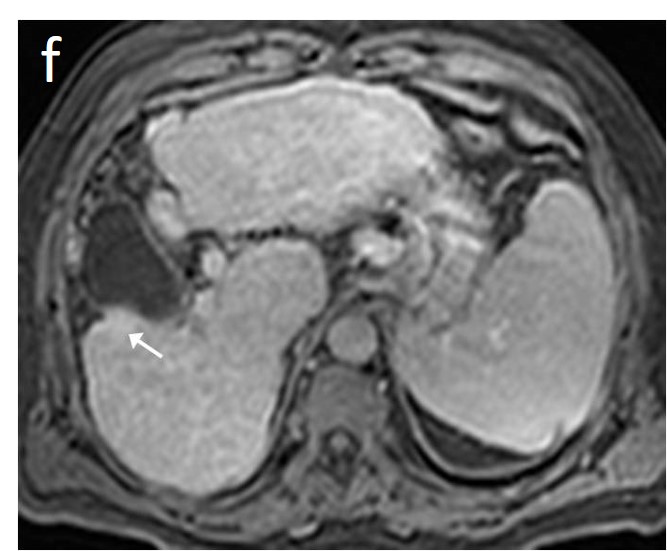

As mentioned before, the radiological hallmark that enables a confident non-histological diagnosis of HCC is the combination of hypervascularity on the arterial phase and hypoperfusion on the portal phase; as with CT, this “wash-in/wash-out” pattern is indispensable on MRI as well. According to the LI-RADS criteria, no lesion without hyperenhancement on the arterial phase can be definitely characterized as HCC; hyperenhancement has to be “non-rim”, i.e., not predominantly peripheral (in order to differentiate from metastases or cholangiocarcinoma) [51]. However, up to 40% of HCCs show no hypervascularity on the arterial phase, and these mainly represent early or poorly-differentiated HCCs [131,132]. Moreover, 40–60% of small HCCs lack wash-out during the portal phase [133,134] (Figure 10). Additional major and ancillary features are employed to help characterize the lesion and assign a LI-RADS category to it.

Figure 10. Evolution of a cirrhotic nodule into HCC. No suspicious lesions are identified on the T2 (a) and DWI (b) sequence of this 66-year-old man with cirrhosis due to hepatitis B infection. On the follow-up scan, performed 3 months later, increased T2 signal (c) is now observed in a nodule in segment V, which is associated with diffusion restriction (arrow) (d). After contrast administration, arterial enhancements (e) without delayed wash-out (f) are seen; absence of wash-out is frequent in early HCCs.